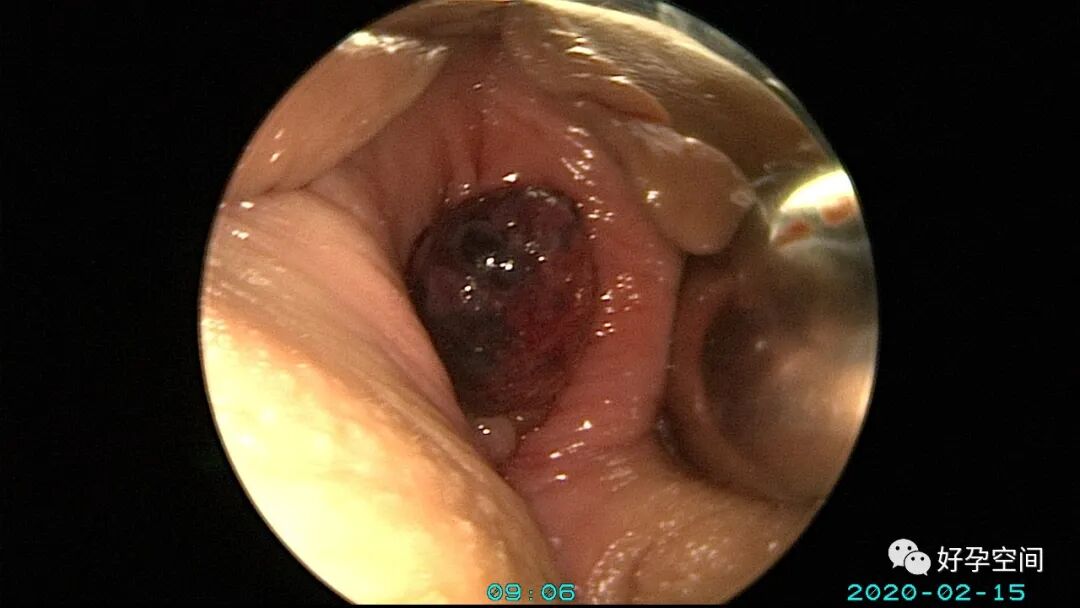

病例3:(病人年龄及取卵个数不详)取卵术后血尿膀胱内血块尿潴留,膀胱灌洗效果不佳,宫腔镜探查膀胱,清除血块,膀胱多处穿刺伤,电凝止血。

病例4:32岁,取卵13枚,取卵术后血尿膀胱内血块尿潴留,膀胱灌洗效果不佳,宫腔镜探查膀胱,清除血块,膀胱底见穿刺伤,电凝止血。